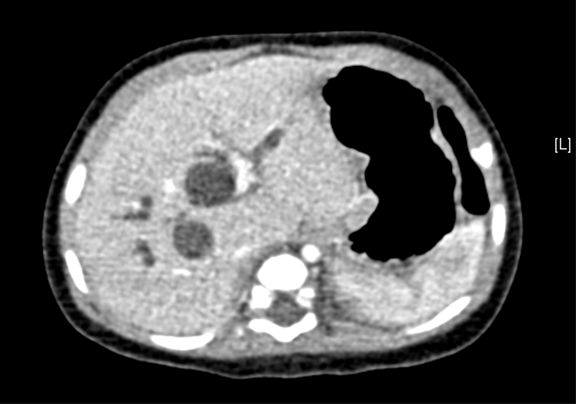

术前CT检查:

动脉期

上腹部增强CT:先天性胆管扩张症(胆总管囊肿)可能性大。

将0.625mm双源薄层CT资料的静脉期和动脉期Dicom格式文件导入海信CAS系统。

通过调节窗宽窗位调整CT序号,对肝实质,胆囊,下腔静脉,肿瘤,肝动脉、门静脉及肝静脉等进行三维重建;系统自动计算肝脏体积。